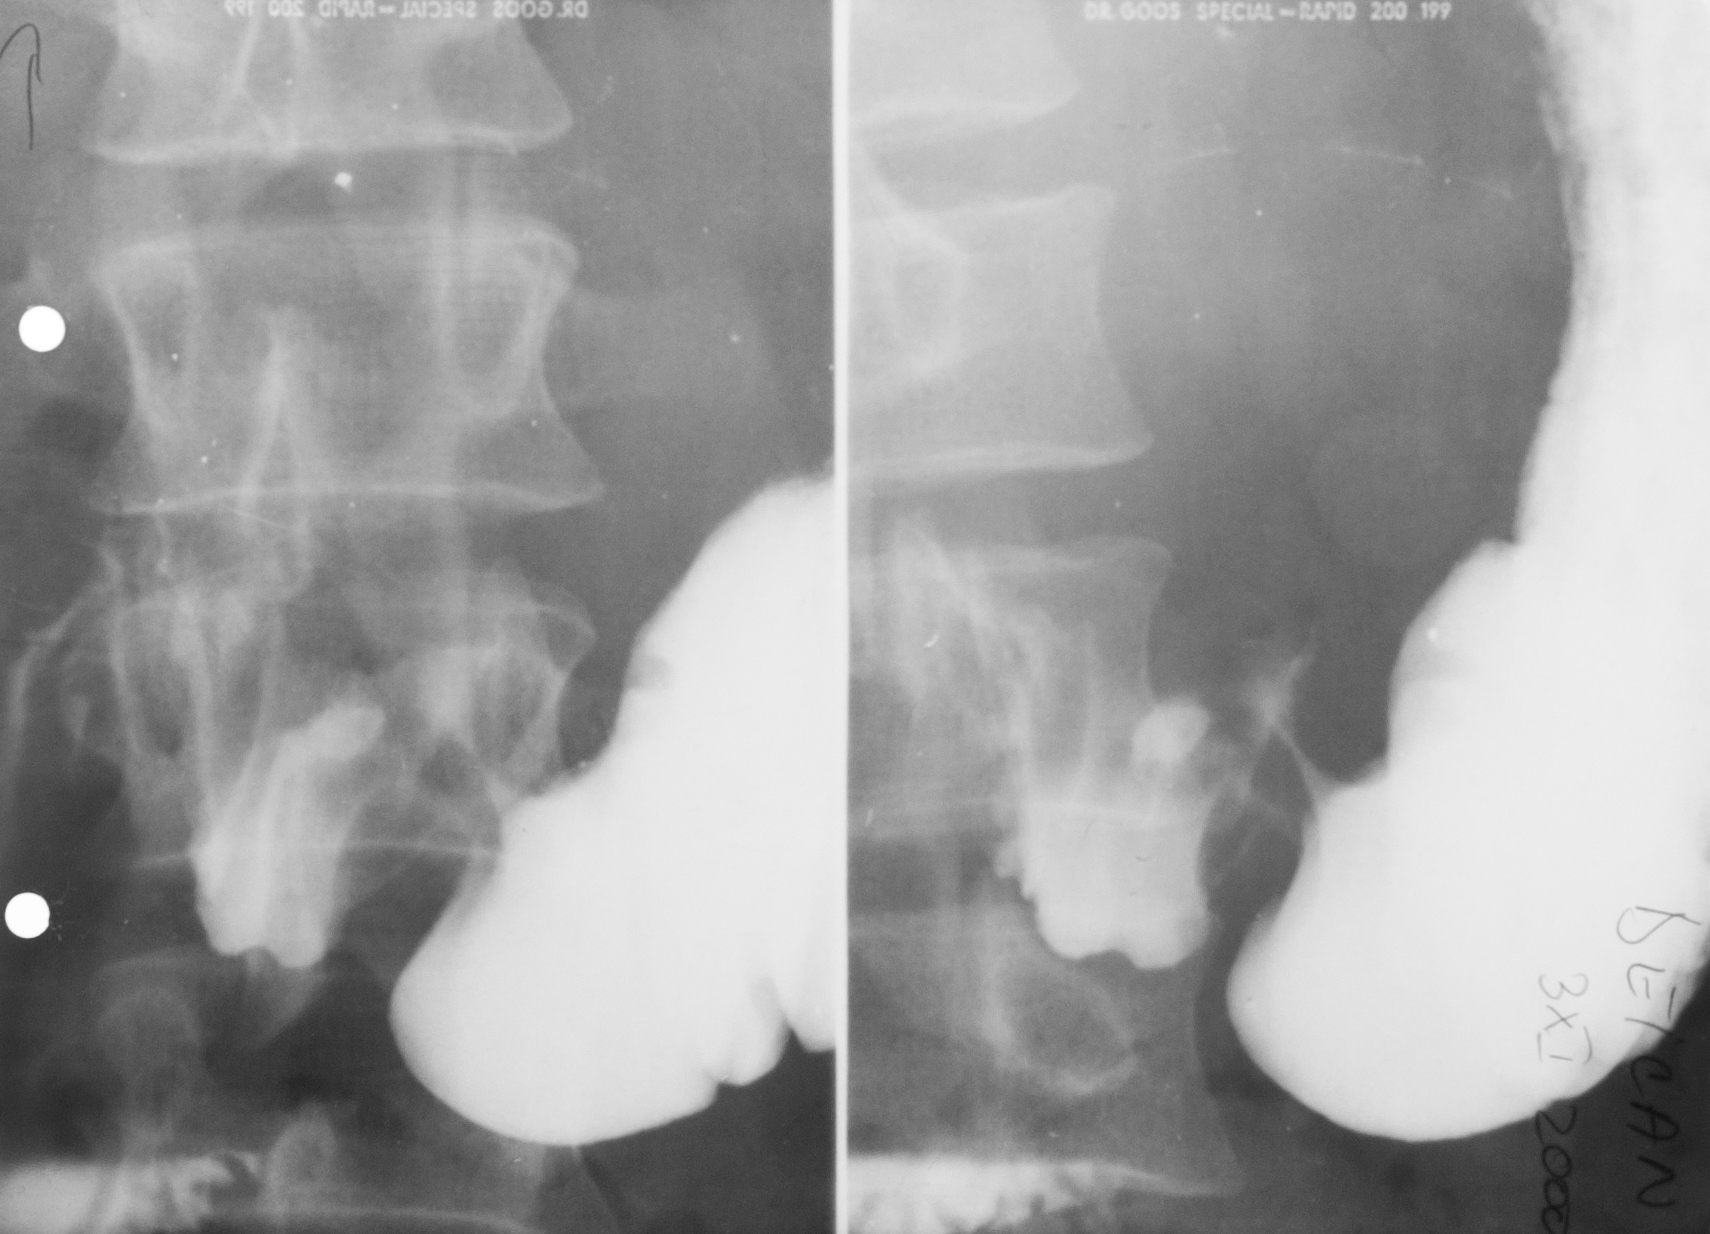

NIȘĂ ÎN LACUNĂ

Examen baritat al corpului gastric

Se observă defecte de umplere,adică dislocuirea substanței de contrast de ceva ce se găsește în lumenul stomacului și anume o masa parenchimatoasă cu contur polilobat.

Cel mai probabil este un proces neoplazic vegetativ de dimensiuni mari,care are la nivelul ei și o ulcerație.Imaginea se numește nișă în lacună.

NIȘA MALIGNĂ ÎN REGIUNEA ANTRALĂ

Nișa malignă este mai mult lată decât adâncă și nu iese din conturul corpului gastric.

Ulcerația este în perete,dar nu iese din conturul peretelui gastric.

ULCERAȚIE CRONICĂ

Se observă,în urma tranzitului baritat,bulbul duodenal cu incizuri la nivelul curburilor,având aspect de treflă,caracteristic pentru ulcerațiile cronice

:NEOPLAZIE INFILTRATIVĂ

Tranzit baritat.Se observă o îngustare semnificativă a lumenului la nivel antral,dând aspect de antru amputat.Nu sunt vizibile pliurile de mucoasă,deci este vorba de o neoplazie infiltrativă.

NIȘĂ LA NIVELUL BULBULUI DUODENAL

Tranzit baritat.La nivelul bulbului duodenal se află o pată persistentă de substanță de contrast,captată la nivelul unei nișe

NIȘĂ DE TIP MALIGN

Nișă de tip malign mai mult lată decât adâncă,situate în regiunea antrală cu pliuri de mucoasă ce converg până în craterul nișei

Tranzit baritat.Bulbul duodenal cu o pată ce persistă pe una din fețele bulbului.Avem de a face cu o nișă de dimensiuni mari la nivelul bulbului

LIMFOM GASTRIC

Imagine lacunară cu contur net linear delimitat,substanța de contrast stă pe această formațiune,înseamnă că există mucoasă gastrică

Proces dezvoltat de la nivelul peretelui,din straturile submucoase

Defect de umplere

DEFECT DE UMPLERE

Defect de umplere. Imagine in monocontrast sus si dublu contrast cele de jos, substanta de constrast este bine lipita de contururile acestui defect de umplere, inseamna ca adera de mucoasa, exista mucoasa gastrica normala.

Într-o formațiune vegetantă carcinomatoasă nu există mucoasă.

STARE DUPA GASTRECTOMIE PARTIALA

Nu avem antru, pilor, canal duodenal, substanta de contrast de la nivelul stomacului ajunge la nivelul jejunului

STARE DUPA GASTRECTOMIE PARTIALA

Cu anastomoza cu jejunul